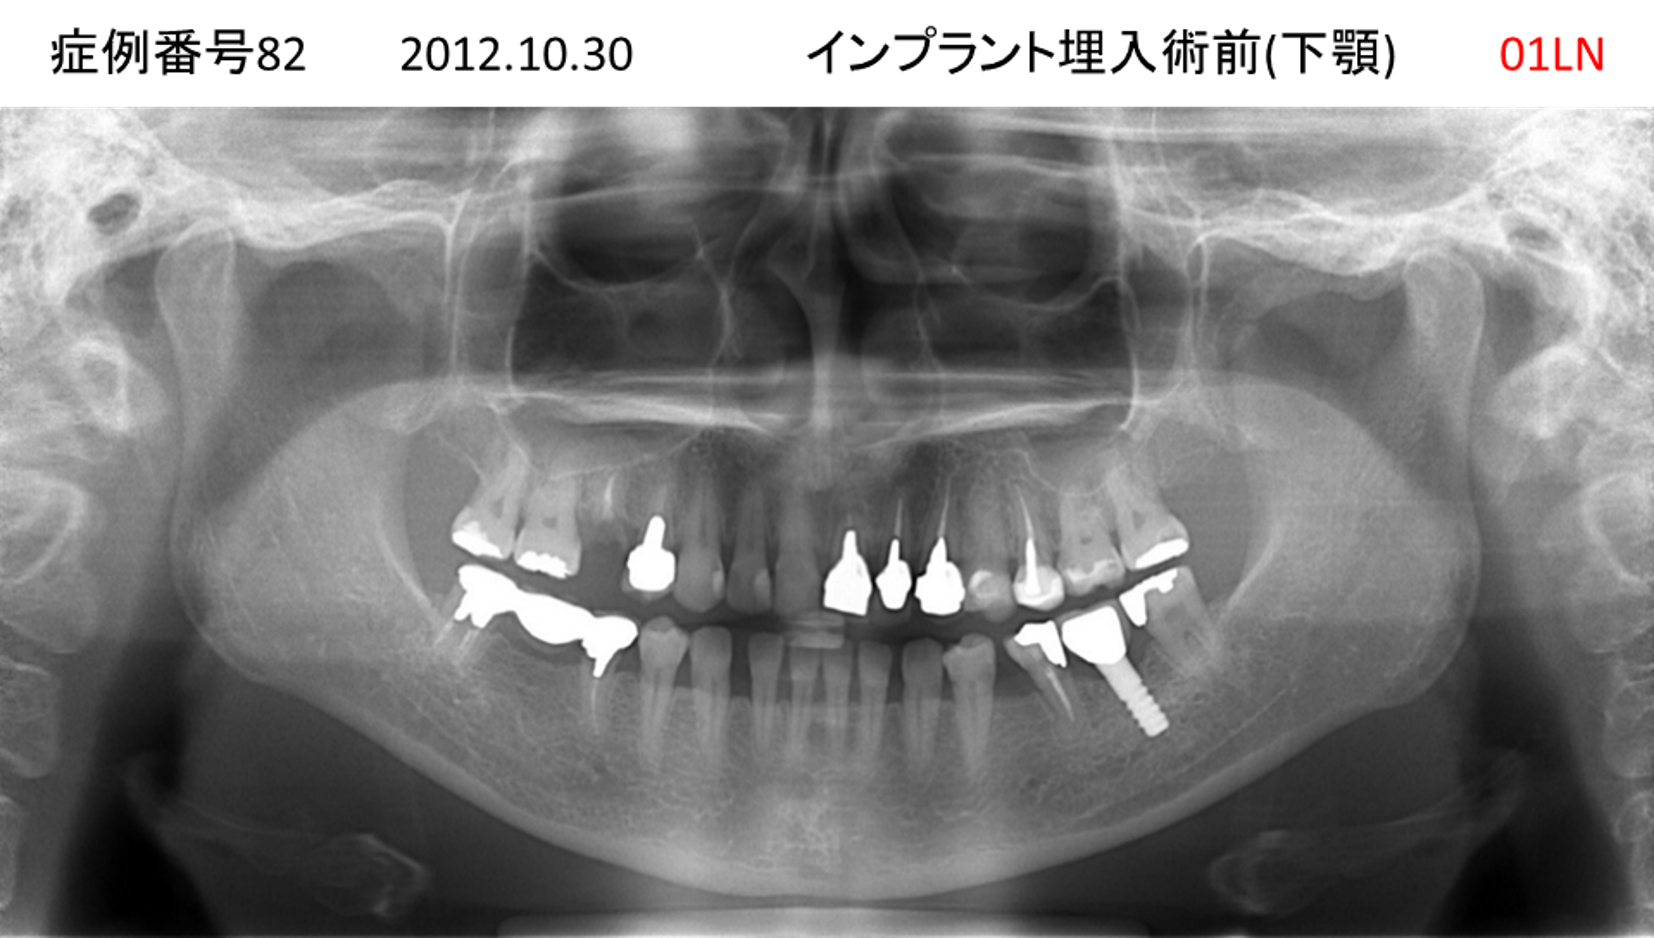

全く噛めない患者様のインプラント症例

| 患者さんの症状(主訴) |

全く噛めない。何とかしてほしい |

| 治療内容 |

サイナスリフト、インプラント、義歯作製(ロケーター) |

| 治療結果 |

好きなものが食べられるようになった。見栄えがとても良くなった。 |

| 治療の注意点(リスク/副作用) |

義歯が壊れた場合、インプラントが壊れた場合は再治療が必要 |